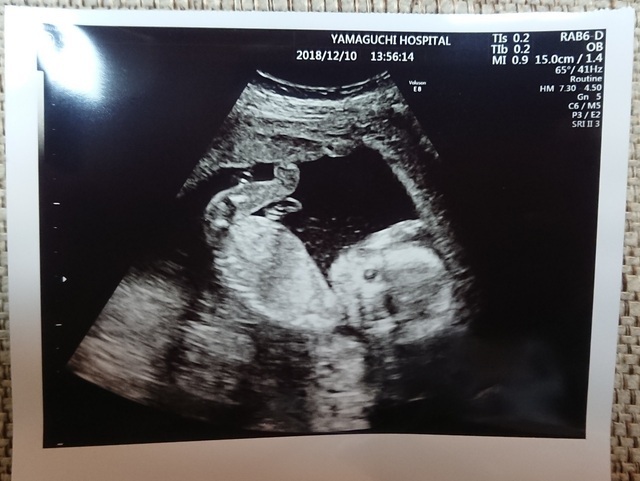

17週0日(17w0d・男の子)|Ayako. さん(32歳)

エコー写真撮影時のエピソード:

戌の日の安産祈願に行った時に周りの妊婦さんがかなりお腹が大きかったのに、私はお腹がなかなか大きくならずに心配していましたが、エコーの赤ちゃんはきちんと大きくなっていて安心できました。

右手をあげて、こちらに挨拶をしているようなポーズが面白くてお気に入りの一枚です。